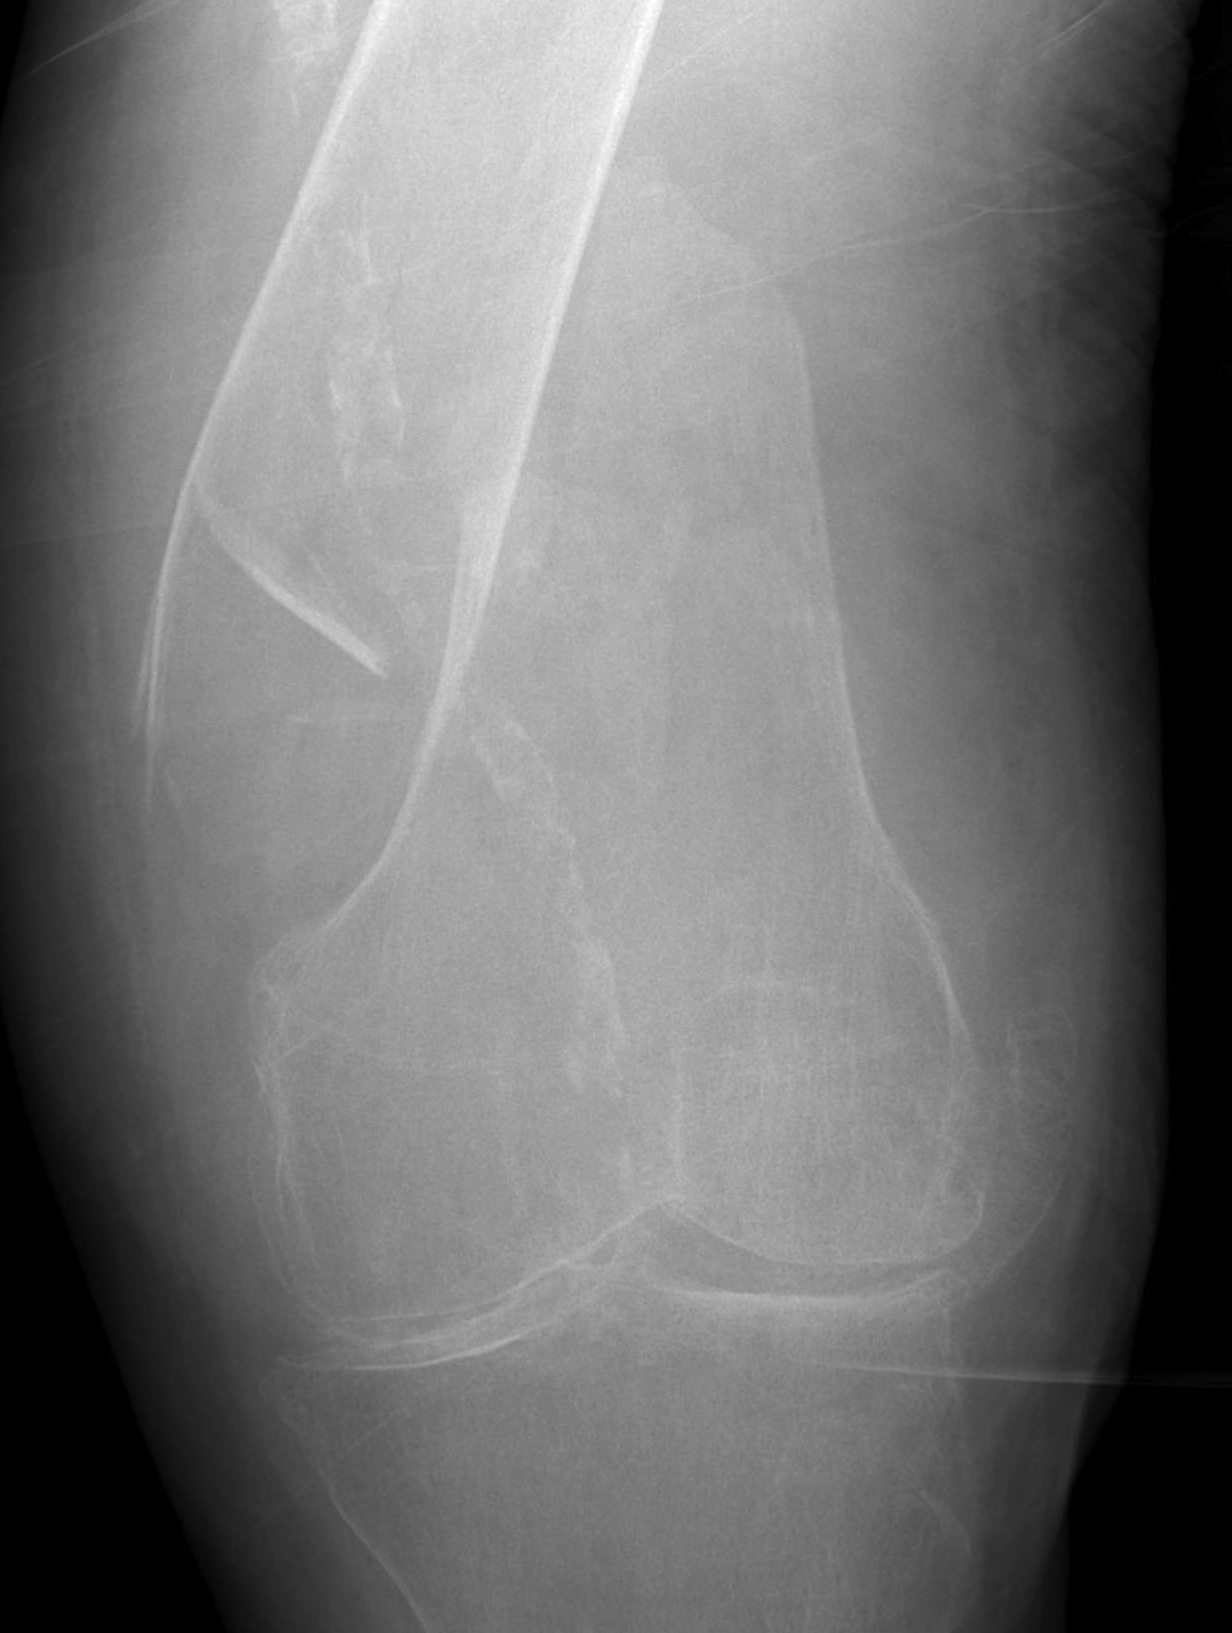

Type C: Complete articular

Xray / CT

Options

Dual Plate

Plate + Retrograde nail

Distal femur replacement